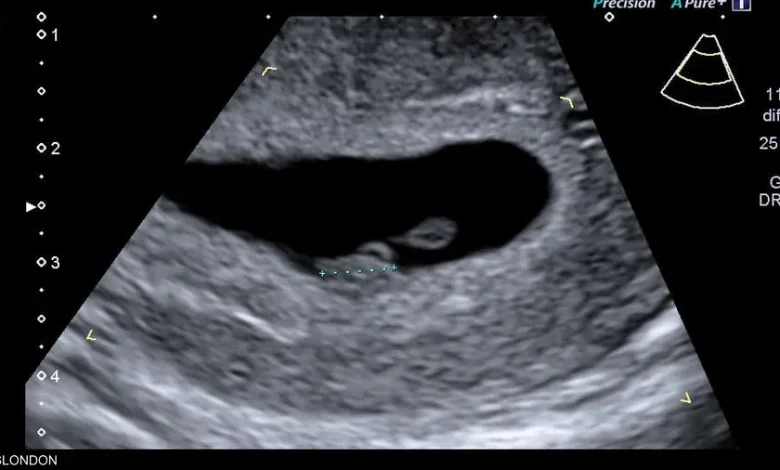

لكن مجموعة من الباحثين الأميركيين تقول إن استخدام الذكاء الاصطناعي لتحليل صور الموجات فوق الصوتية يمكن أن يتنبأ بموعد ميلاد الطفل بدقة تصل إلى 95 في المئة.

وباستخدام برنامج تم تطويره وتدريبه باستخدام أكثر من مليوني صورة بالموجات فوق الصوتية لنساء أنجبن أطفالهن بين عامي 2017 و2020، قام العلماء بقياس مدى قدرة الذكاء الاصطناعي على تقدير ما إذا كان الطفل سيرى النور في موعد ولادته أم لا.